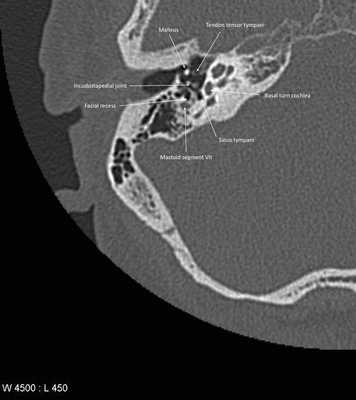

КТ-анатомия височных костей

Компьютерная томография височных костей в норме показывает следующие анатомические структуры:

- Ровные, четки стенки;

- Физиологическая ширина просвета;

- Склеротический тип строения ячеек;

- Нормальная пневмотизация;

- Мягкотканые структуры устья слуховой трубы;

- Четкая визуализация слуховых косточек;

- Нормальная конфигурация прохода;

- Четкие ровные стенки.